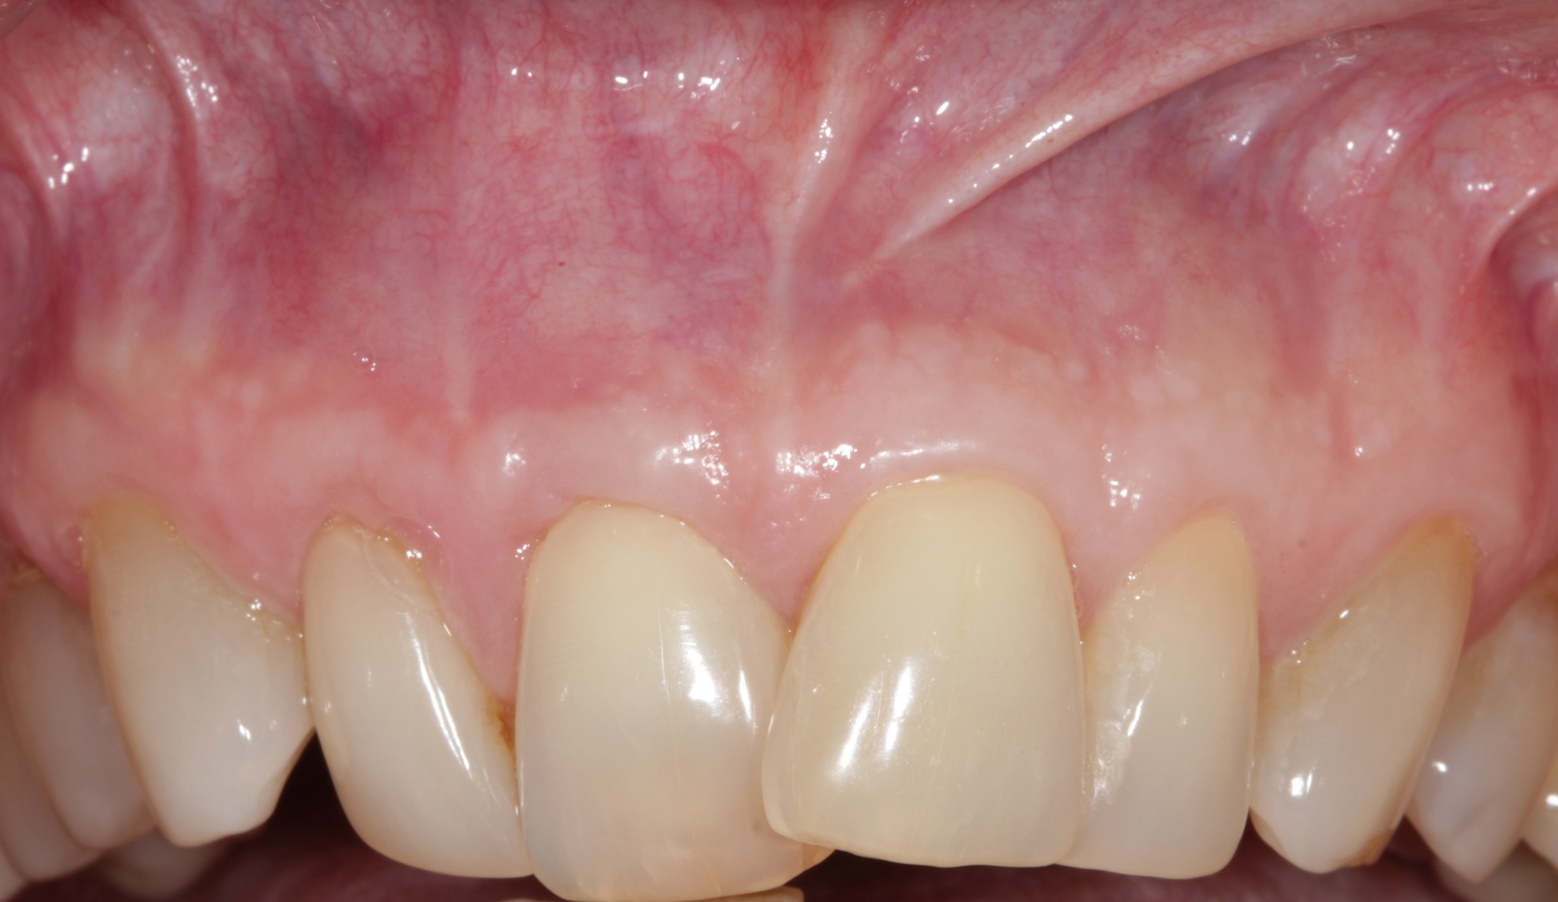

The clinical reproducibility of the root-coverage procedure associated with an increase of the zone of keratinized tissue depends on (Figure 9 through Figure 11) several factors.

Fig 9. Two years postoperative. A complete root coverage and increase of the zone of attached and keratinized tissue is observed.

Figure 9

Fig 10. Cross-sectional view of the preoperative and postoperative (2 years). A three-dimensional increase of zone of keratinized and attached tissue is observed, restoring the lost attachment apparatus and correcting the gingival deformity in height and width.

Figure 10

Fig 11. Cross-sectional view of the preoperative and postoperative (2 years). A three-dimensional increase of zone of keratinized and attached tissue is observed, restoring the lost attachment apparatus and correcting the gingival deformity in height and width.

FIgure 11